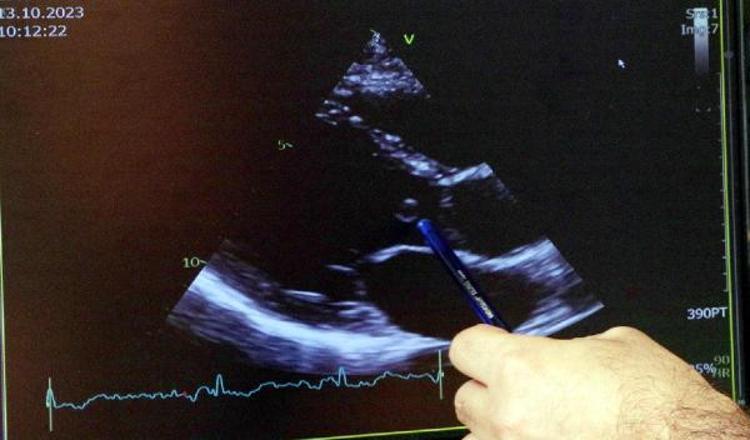

Henüz 10 aylıkken kanama bozukluğu hastalığı olan Von Willebrand teşhisi konulan 31 yaşındaki inşaat mühendisi Emrullah Çiftçi, en ufak bir yaralanmada dahi hayati risk yaşadı. Geçtiğimiz ay ise kalp kapağı iltihabı nedeniyle en kanlı kalp ameliyatlarından birini olması gerektiğini öğrendi. Gittiği birçok hastane çok riskli olduğu için onu ameliyat etmeyi kabul etmedi. İstanbul'a gelen Çiftçi'nin enfeksiyon nedeniyle harap olan kalp kapağı, Marmara Üniversitesi Pendik Eğitim ve Araştırma Hastanesi Kalp Damar Cerrahisi, Hematoloji ve Yoğun Bakım ekiplerinin mucizevi çabası sonucu başarıyla değiştirildi. Toplamda 22 ünite kan verilen genç mühendis, yaklaşık 5 saat ameliyatta kaldı. Kalp ameliyatı sonrası sızıntı riski nedeniyle yoğun bakımda 24 saat kalbi açık bir şekilde izlendi. Doktorları taşıdığı risk nedeniyle ilk ameliyat sonrası gece yarısına kadar hastaneden ayrılmadı. Kanamaya bağlı sızıntı giderilerek göğüs duvarı ertesi gün yapılan ikinci ameliyatla kapatılabildi. Ameliyatı gerçekleştiren Kalp Damar Cerrahisi Uzmanı Prof. Dr. Koray Ak, Çiftçi'nin tıp literatürüne gireceğini söyledi. Durdurulamayan kanama riski nedeniyle sürecin başından sonuna ekipte yer alan Hematoloji Uzmanı Doç. Dr. Asu Fergün Yılmaz ise hemofili, Von Willebrand gibi kanama bozukluğu hastalarının, uygun merkezlerde iyi ekiplerle en büyük ameliyatları dahi olabileceklerini, bu nedenle hastaların bu tedavilerden mahrum bırakılmaması gerektiğini vurguladı.

Özellikle hemofili hastalarında açık kalp ameliyatı deneyimlerinin bulunduğunu ancak bunların genellikle koroner by-pass tarzı ameliyatlar olduğunu kaydeden Prof. Dr. Koray Ak, "Tabii burada hem Von Willebrand hastalığı hem de hastalığın infektif endokardit olması bizi oldukça endişelendirdi. Normalde infektif endokardit tek başına oldukça kompleks bir hastalık zaten. Bunun üzerine oldukça nadir görülen kanama bozukluğu hastalığı da eklenince bu vakayı çok ilginç ve yönetimi zor bir vaka şeklinde karşımıza getirdi. Birçok merkezle görüşmüş. En sonunda bize geldiği zaman biz konsey toplantısı yaptık. Kan bankası ve hematoloji laboratuvarı açısından mevcut faktör envanterimizi gözden geçirdik ve ameliyatın planlamasını yaptık. Aslında ilk amacımız kapağı tamir edebilmekti, aort kapak tamiri de yaptığımız ameliyatlardan biri. Fakat Emrullah'ın kalp kapağı enfeksiyona bağlı ciddi derecede harap olmuştu. Koruma şansımız yoktu ve mekanik protez kapakla değiştirdik" dedi.

Açık kalp ameliyatı sonrası yoğun kanama problemi yaşadıklarını ve hastayı göğüs duvarı açık bir şekilde yoğun bakıma aldıklarını anlatan Prof. Dr. Ak, "Göğsü kapatamama durumu ortaya çıktıktan sonra, kanamayı kontrol altına alabilir miyiz diye çok büyük bir endişe yaşadık. Hematoloji hocamız da hastanın başındaydı. O gece, gece yarısına kadar hastanede kaldık. Yaklaşık 24 saat bu şekilde takip ettik ve bu şekilde bile sızıntıların devam etmesi nedeniyle tekrar ameliyata aldık. Göğsü ikinci ameliyatta kapattık. Bu esnada da sürekli kan ve kan ürünü transfüzyonu ile faktör replasmanı yaptık. Toplamda 20-22 ünite kan kullandık. Normalde belki 1 ünite, belki hiç kullanmayız" ifadelerini kullandı.